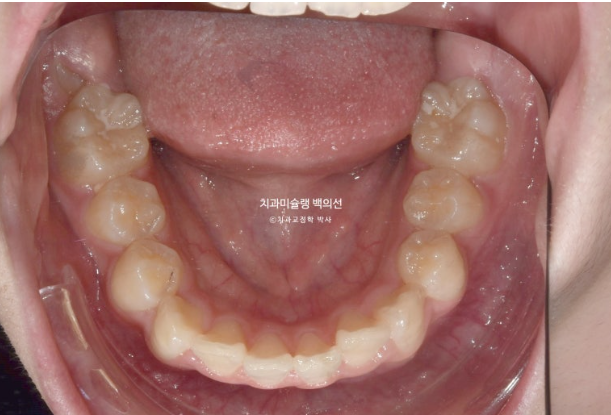

23.02

23년 2월 교정치료를 위해 온 중학생 환자분입니다.

덧니와 중심선 불일치, 과개교합 등이 눈에 띕니다.

덧니가 있으면 덧니쪽으로 중심선이 돌아가게 됩니다.

교정치료로 치아중심선을 코와 인중에 맞춰야 합니다.

앞니 뻗침도 있어서 약간의 돌출입도 있습니다.

덧니와 돌출 해소를 위해 작은어금니 발치교정이 필요합니다.

단 위에만 2개 발치 치료계획을 세워습니다.

아래 작은어금니까지 총 4개를 빼면 입이 너무 많이 들어가게 되기 때문입니다.

클리피씨 교정 선택하셨고 치료 들어갔습니다.